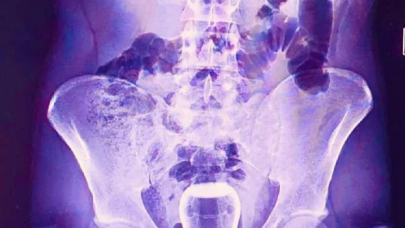

SAĞLIK

Sağlık